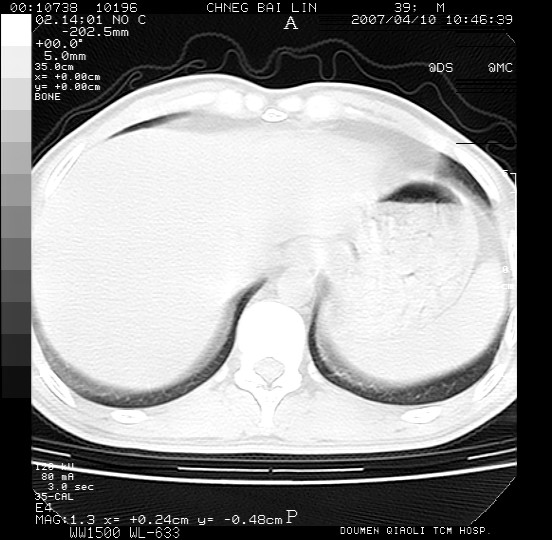

男,39岁。10天前自觉感冒,曾输液一次内容不详曾有吸毒史。现有咳嗽、咳痰胸闷。

双肺弥漫性网状、磨玻璃样病灶,边界不清。有吸毒史。首先考虑机遇性肺部感染。

两肺弥漫分布的网状毛玻璃状阴影,边缘模糊不清,纵隔未见明显淋巴结肿大

诊断:机遇性肺部感染

鉴别诊断:1特发性肺纤维化,主要部位在两肺下叶胸膜下网状,毛玻璃状及蜂窝状阴影,临近胸膜增厚,该病征象不太符合